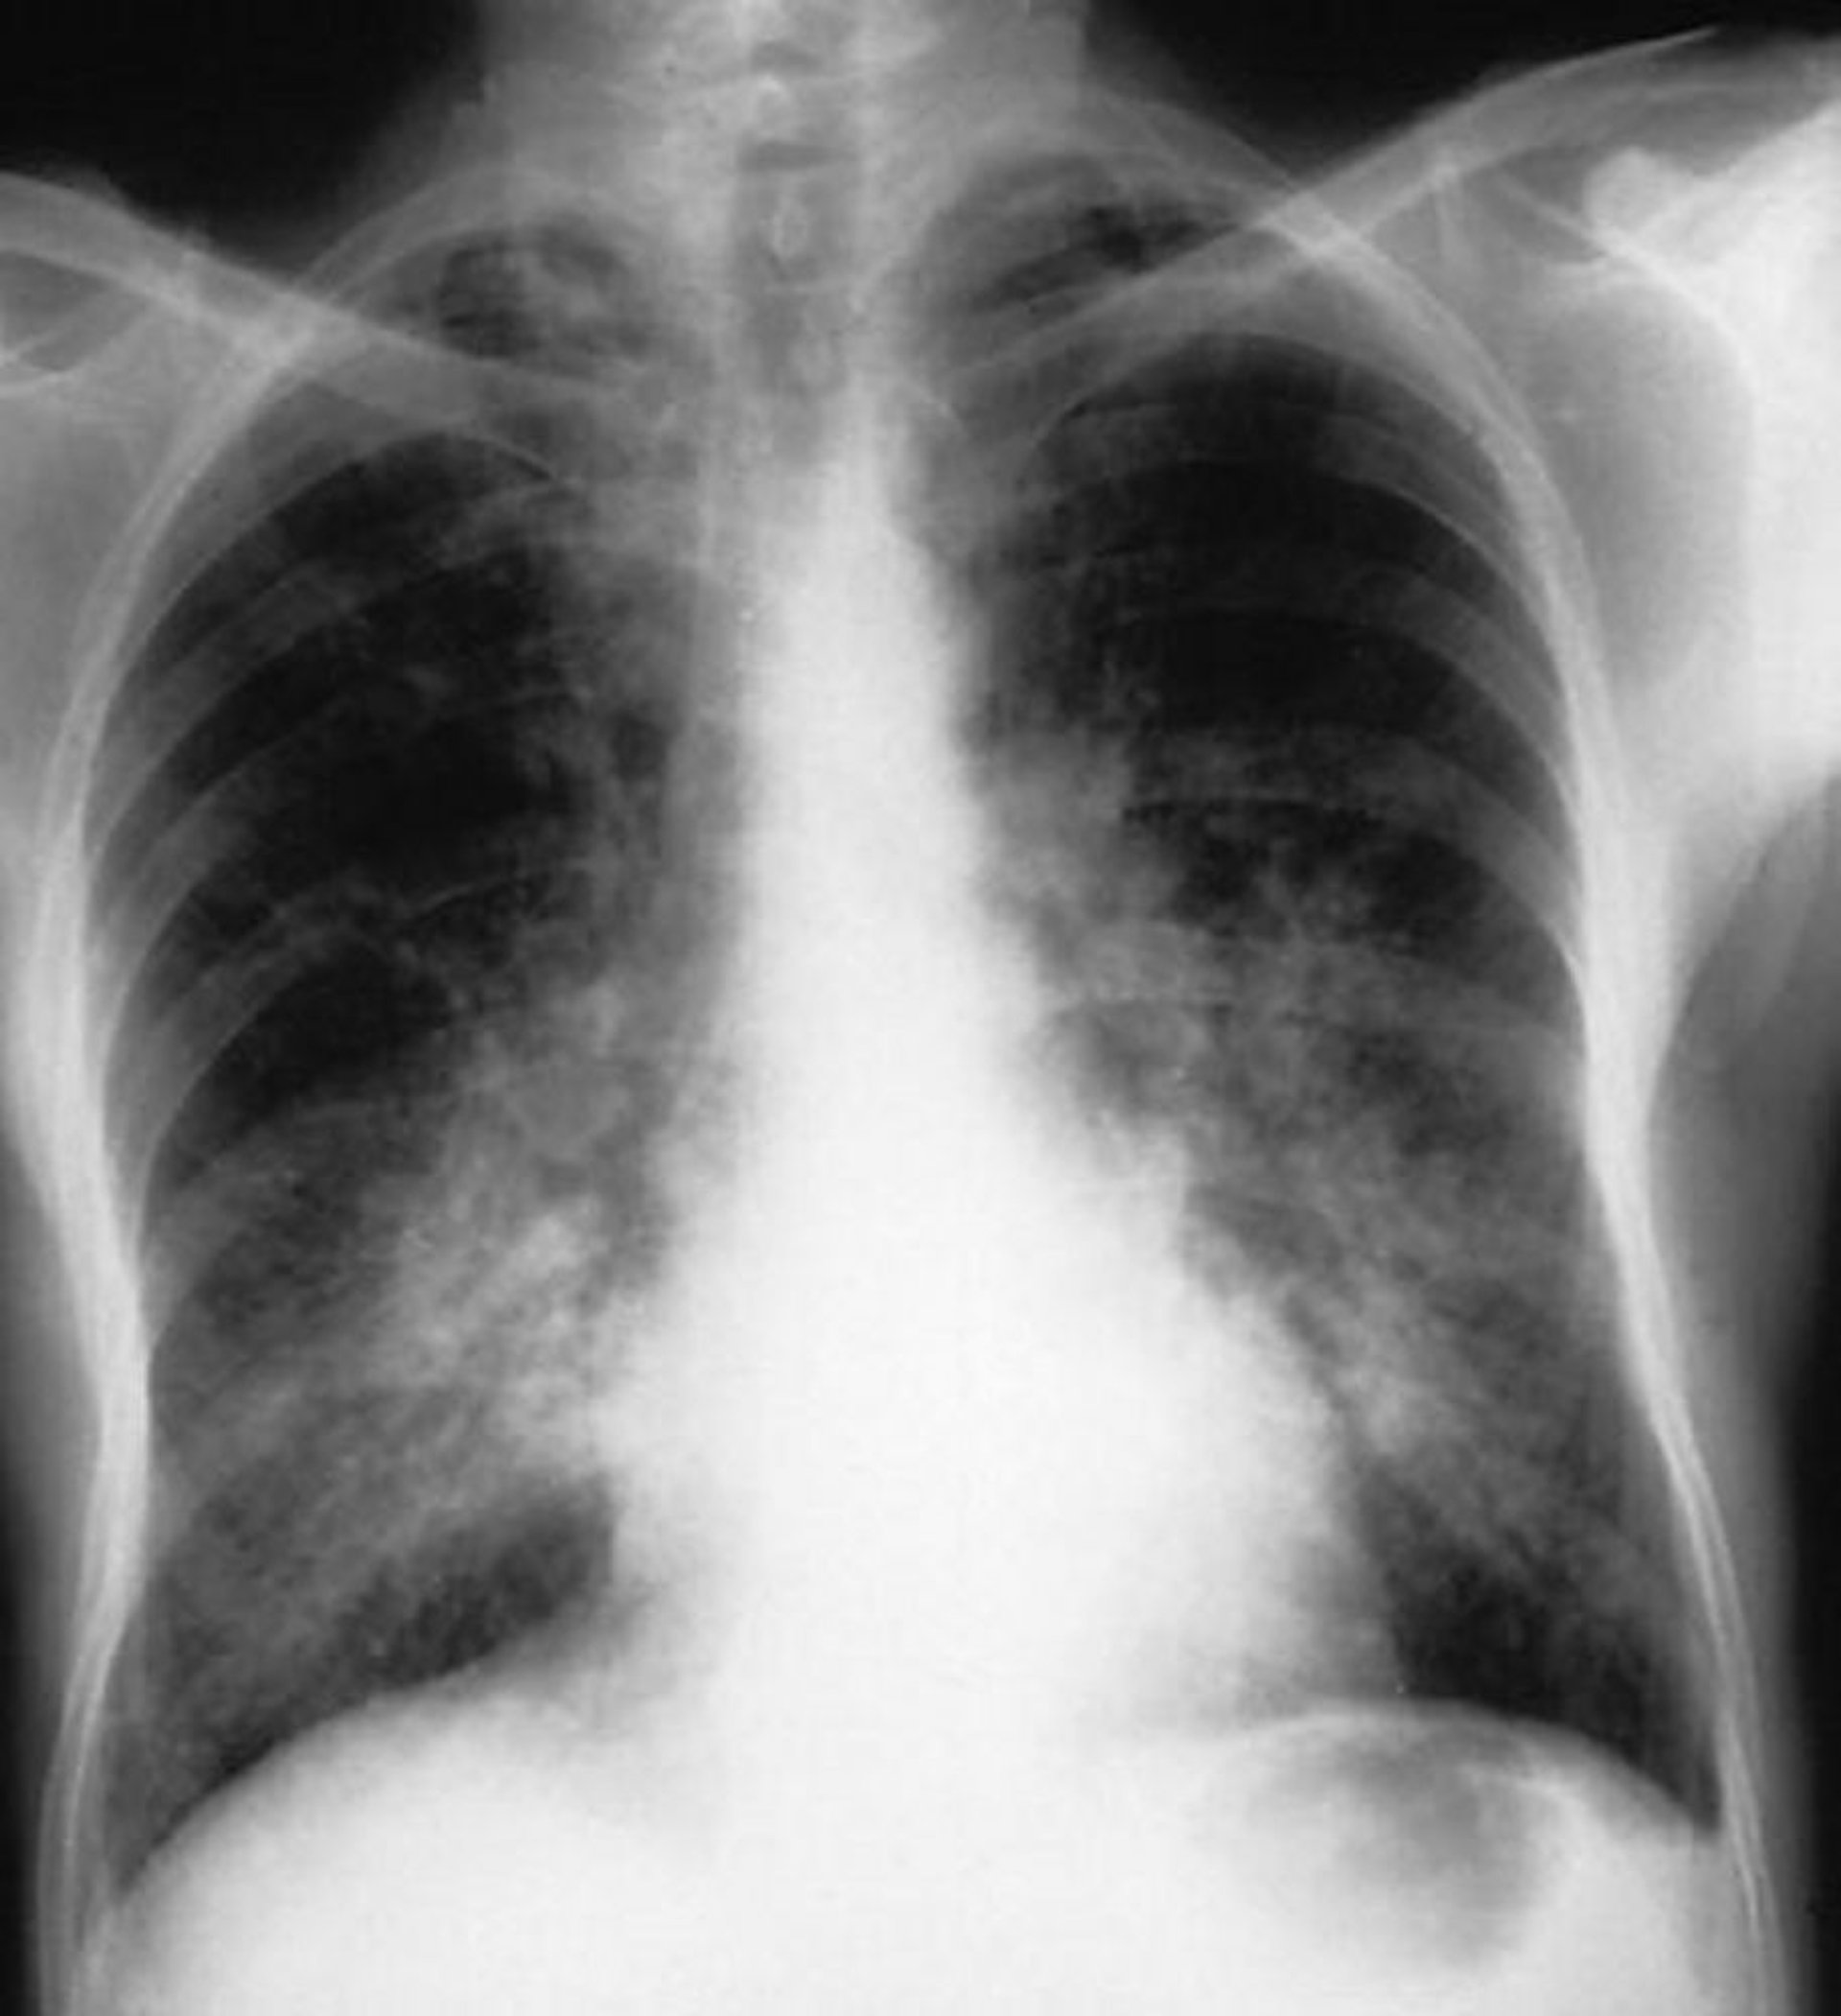

Hemorragia alveolar

Essa radiografia do tórax mostra opacidades alveolares bilaterais em um paciente com hemorragia alveolar.

By permission of the publisher. From Cohen A, Glassock R. In Atlas of Diseases of the Kidney: Glomerulonephritis and Vasculitis. Editado por R Schrier (editor da série), RJ Glassock, and AH Cohen. Philadelphia, Current Medicine, 1999.